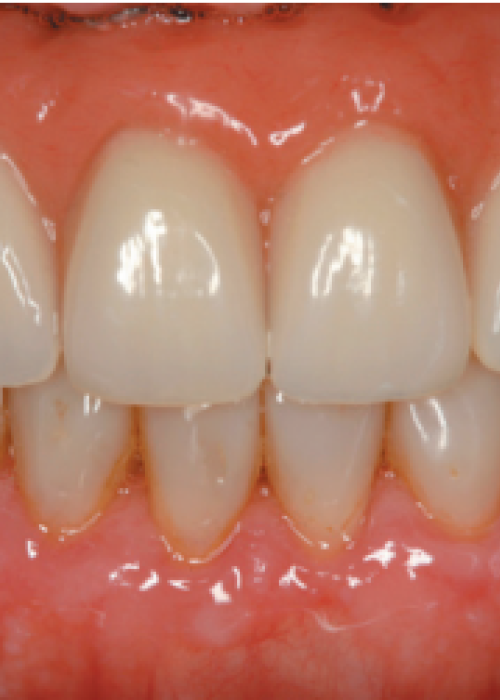

Explantación de implante mal posicionado en sector estético y regeneración posterior con injerto en bloque

Implant explantation poorly positioned in an aesthetic sector and subsequent regeneration with block grafting. Clinical case